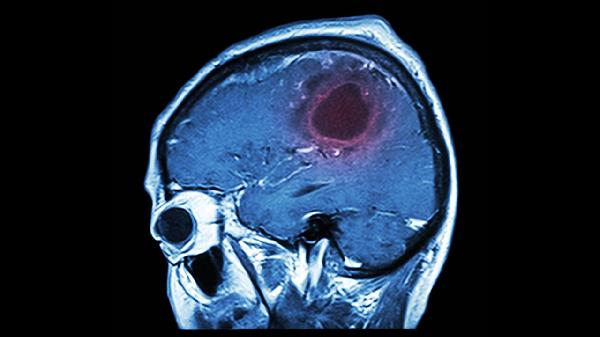

神经内科主要排查器质性病变。短暂性脑缺血发作是常见诱因,由于脑血管暂时性供血不足导致记忆功能短暂中断,患者可能出现言语含糊或肢体麻木。癫痫发作尤其是颞叶癫痫可能伴随数分钟记忆空白,脑电图检查可辅助诊断。偏头痛伴随的短暂性全面遗忘症多持续数小时,通常无须特殊治疗。脑震荡等轻度脑外伤也可能引发逆行性遗忘,需结合影像学排除颅内出血。